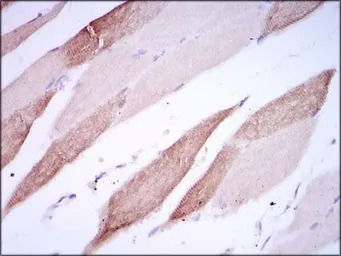

IHC-P analysis of human striated muscle tissue using GTX60629 CD166 antibody [5B3].